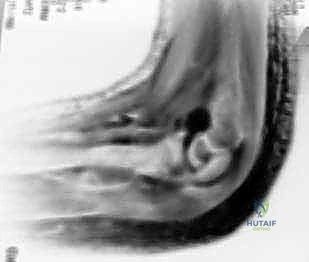

التصوير بالأشعة السينية (X-rays)

الأشعة السينية هي الأداة الأساسية للتشخيص. يتم أخذ صور في وضعيات متعددة (أمامية خلفية AP، وجانبية Lateral، وربما مائلة Oblique).

لماذا الكسر مخادع؟ في الأطفال الصغار، تكون أجزاء كبيرة من مفصل الكوع عبارة عن غضاريف لم تتحول إلى عظم صلب بعد (لم تتعظم). الأشعة السينية لا تظهر الغضاريف، بل تظهر العظام فقط. لذلك، قد يبدو الكسر في الأشعة صغيراً جداً (مجرد قشرة عظمية صغيرة مكسورة)، بينما في الواقع، هناك كتلة غضروفية كبيرة جداً (تحتوي على سطح المفصل وصفيحة النمو) قد انفصلت تماماً وتدور حول نفسها.

هنا تتجلى خبرة الجراح. الطبيب غير المتخصص قد يرى الأشعة ويقول للآباء "إنه كسر بسيط يحتاج لجبس"، بينما الخبير مثل أ.د. محمد هطيف يدرك من خلال النظرية التشريحية وخبرته الطويلة أن هذا الكسر غير مستقر ويحتاج لتدخل جراحي.